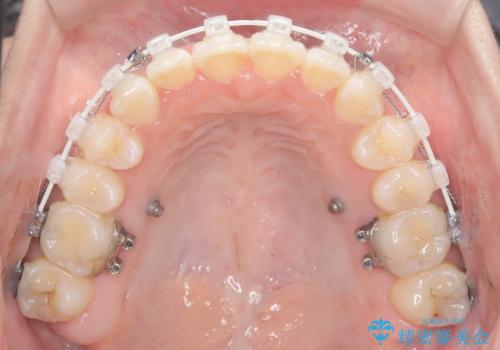

- 治療計画

治療では、審美ワイヤーを使用し、目立ちにくく配慮しながら矯正を進めました。上顎にリンガルアーチと矯正用アンカースクリューを用いて臼歯部を安定的に遠心移動させ、歯列全体のスペースを確保しました。その後、回転していた前歯を正しい位置に配列し、全体的な歯並びの改善を行いました。治療中は、装置の適切な管理と口腔衛生を徹底することが重要でした。結果として、見た目だけでなく機能的にも優れた歯列を実現することができ、患者様にもご満足いただけました。